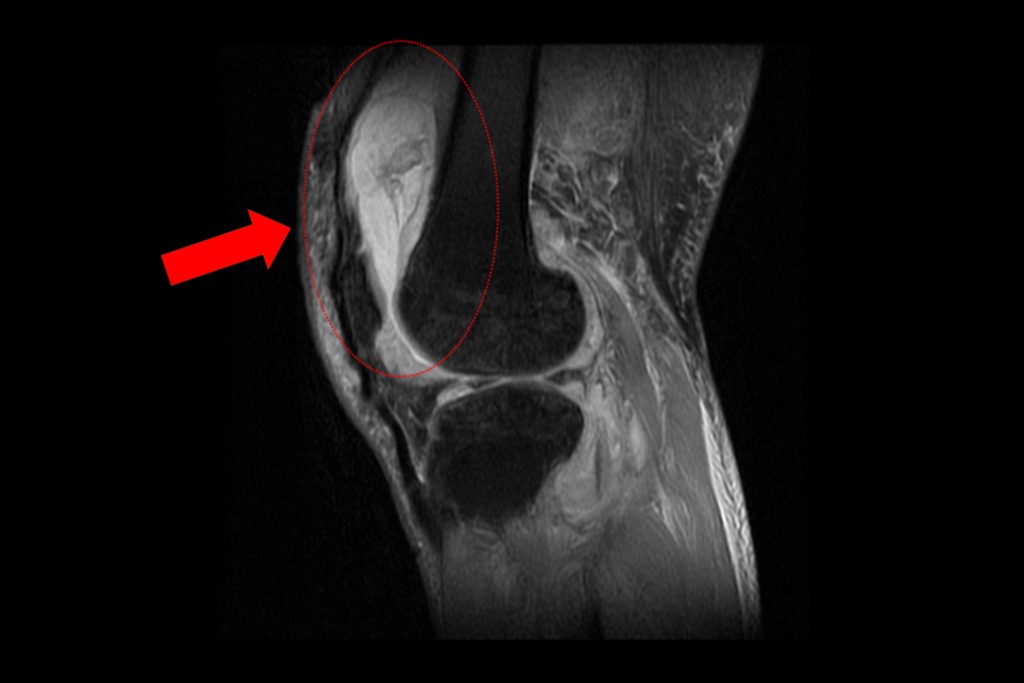

關節中心主任周立展抽取膝關節液化驗後發現,白血球數值雖偏高,並非典型的細菌感染,懷疑有其他原因。安排病人住院,X光與磁振造影檢查,顯示膝蓋內大量積液並化膿,屬於嚴重關節感染。

周立展避免病人感染惡化,緊急施行微創關節鏡清創手術,檢體送病理化驗後發現結核分枝桿菌,顯示並非單純膝蓋退化。痰液培養出結核菌,證實為「肺結核合併肺外感染」。